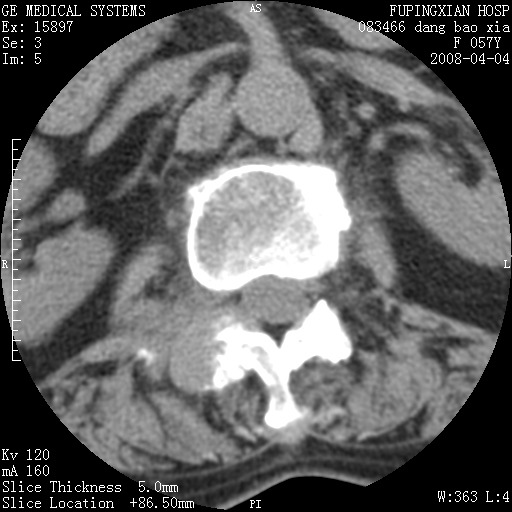

标题: CT12677:女性,57岁,疼痛数月。 [打印本页]

标题: CT12677:女性,57岁,疼痛数月。

考虑椎体恶性肿瘤可能大

考虑骨巨细胞瘤可能性大

椎体及附件骨质破坏同时伴软组织肿块,首先考虑恶性肿瘤。

骨组织起源,膨胀,软组织肿块=恶性改变:首选骨巨,其次转移瘤,再次脊索瘤

椎体及附件溶骨性破坏,周围巨大软组织肿块,首先考虑转移瘤。